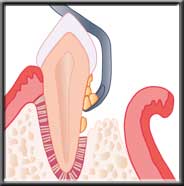

In more moderate cases, there is actual bone loss, and deeper pockets. Non-surgical scaling and root planing may remove the calculus from these deeper pockets but because of limited and difficult access in reaching the bottom of the pocket some of these cases may need flap surgery.This allows us to gain access to clean the root. With this procedure, an incision is made between the gum and tooth, and the gum moved back away from the neck of the tooth and the edge of the bone. We can then easily see the deep calculus, and adequately clean the tooth.

Flap reflected to access deep plaque and calculus |